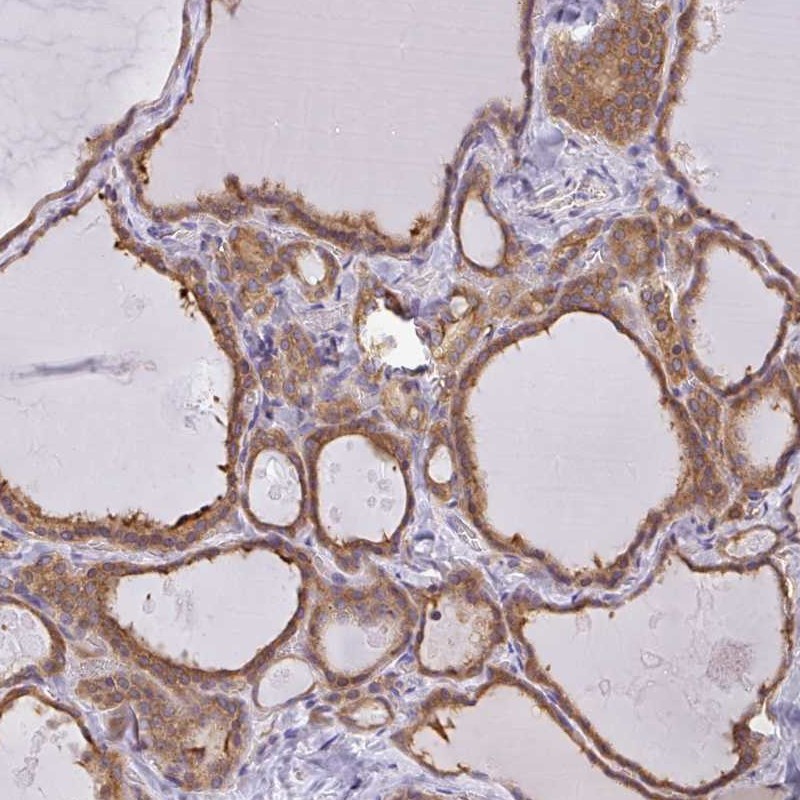

Immunohistochemical staining of human thyroid gland shows moderate cytoplasmiuc positivity in glandular cells.